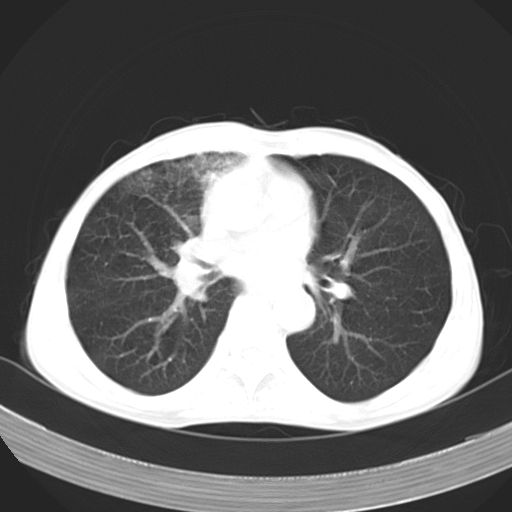

以下是引用苯小孩在2007-5-24 12:47:00的发言:[br]右侧肺门处不均匀密度软组织块影,远端肺组织见斑片模糊影,纵隔内淋巴结明显肿大,边界不清.<纵隔窗第12层面支气管内似见软组织结节>[br]考虑:1、右侧中央性肺癌并阻塞性肺炎并纵隔淋巴结转移可能性大.建议强化或纤支镜进一步检查.[br]2、隆突下淋巴结肿大/食道病变?请做鉴别检查.

以下是引用zhangzhongshou在2007-5-24 12:55:00的发言:[br]1、右肺中叶中心型肺癌并右肺门、隆突下、纵隔淋巴结转移。右肺中叶阻塞性肺炎。

以下是引用jw-830在2007-5-24 15:24:00的发言:[br][br] [br] 考虑右肺中央型肺癌并阻塞性炎症,右肺门及纵隔淋巴结转移。 [br] [br][br]